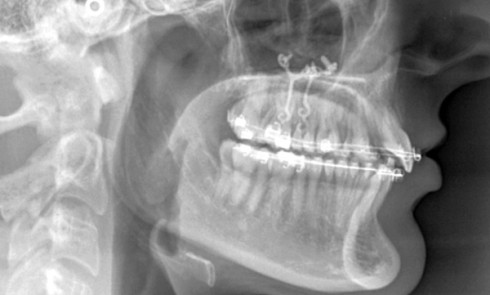

Article réservé à nos abonnés Classe II ortho-chirurgicale ou « l’appétit vient en mangeant »

Madame P., âgée de 43 ans, consulte pour la première fois en octobre 2012 et nous dit : « J’ai l’impression que mes...